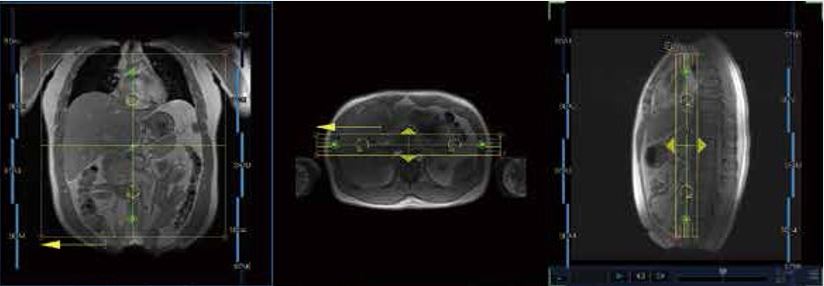

Спрощення процедури планування діагностики призводить до збільшення ефективності, скороченню часу кожного дослідження та покращення досвіду для пацієнта. Поєднання автоматичному вибору котушок у меню послідовностей та приємних для пацієнта котушок Atlas SPEEDER дає якісну та комфортну діагностику.

Спростіть рутинне налаштування котушок та робочий процес, використовуючи автоматичний вибір котушки для візуалізації з панелі вибору котушок при виборі локатора та автоматизований вибір відповідних елементів котушки для отримання найкращого співвідношення сигнал/шум.

МРТ-системи від Canon Medical Systems дозволяють легко виконувати численні дослідження, дозволяючи позиціонувати пацієнта та використовувати необхідні котушки одним простим кроком.